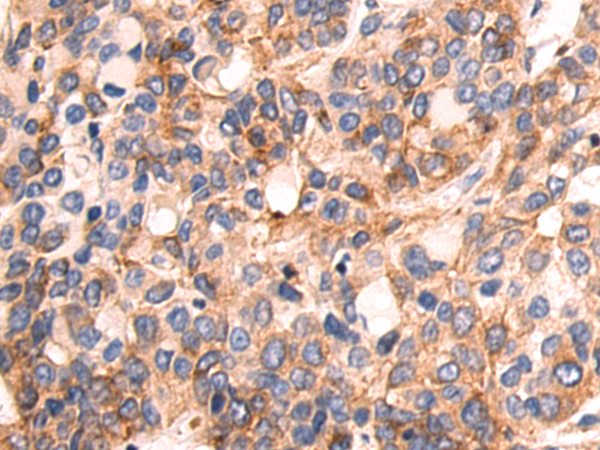

分类: 科研抗体货号: P02571别名: HVLP应用: WB,IHC反应种属: Human